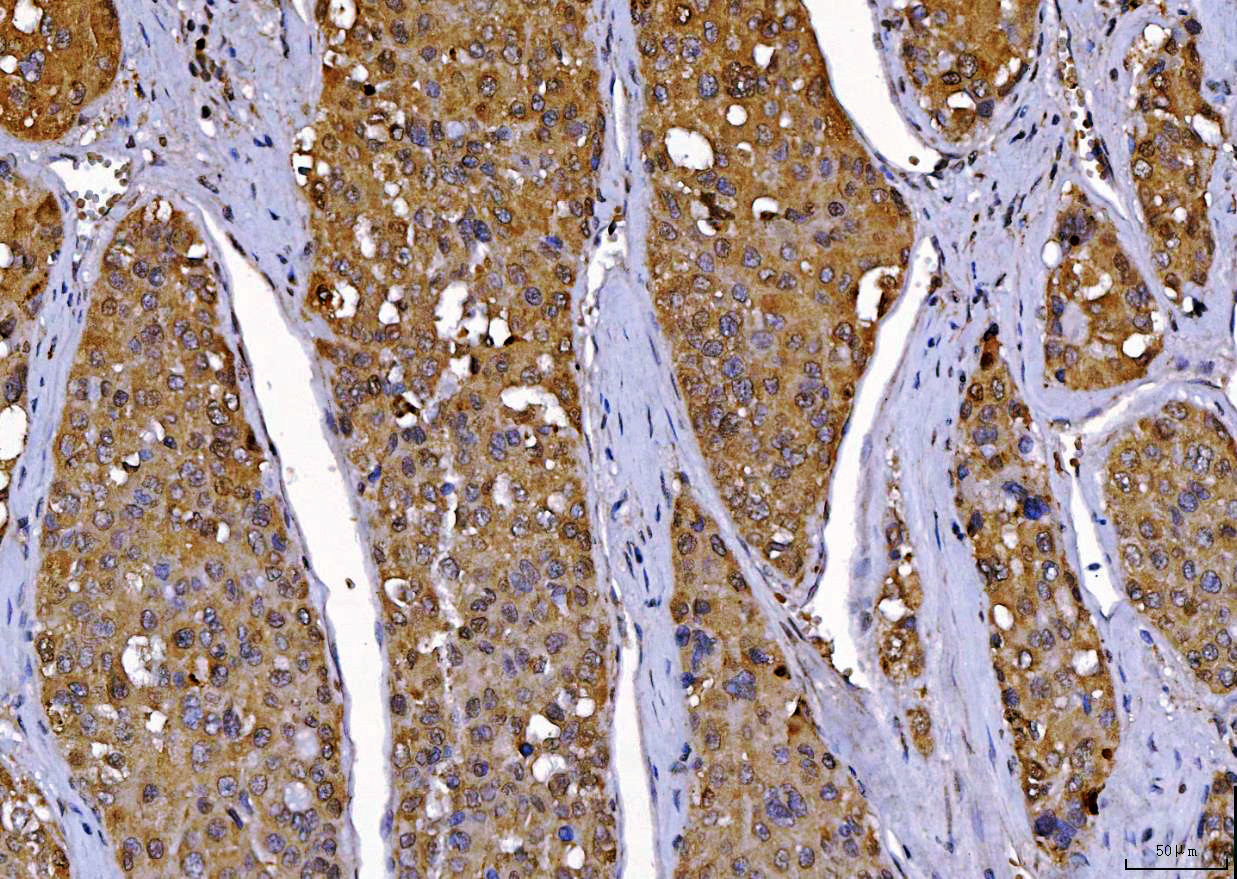

IHC analysis of CDK2 using anti-CDK2 antibody (M00166-4).

CDK2 was detected in a paraffin-embedded section of human Laryngeal squamous cell carcin tissue. Biotinylated goat anti-mouse IgG was used as secondary antibody. The tissue section was incubated with mouse anti-CDK2 Antibody (M00166-4) at a dilution of 1:200 and developed using Strepavidin-Biotin-Complex (SABC) (Catalog # SA1021) with DAB (Catalog # AR1027) as the chromogen.